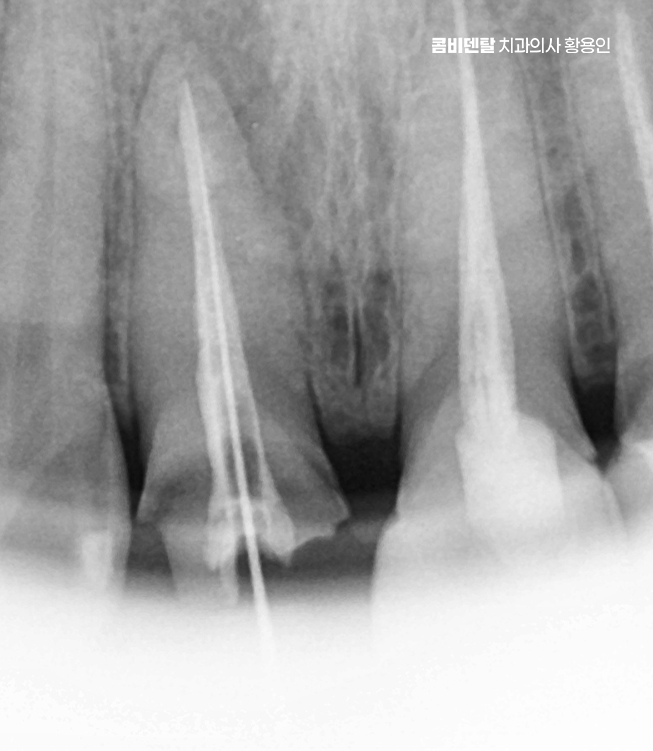

신경치료는 치아 내부의 염증이나 감염된 신경을 제거하고, 뿌리 속을 소독해서 밀봉하는 치료로 앞니는 뿌리가 하나인 경우가 대부분이라 어금니보단 비교적 간단하지만, 이미 보철을 한 치아는 구조적으로 약해져 있기 때문에 세심한 처치가 필요한데 뿌리 일부가 약해져 있거나 균열이 생겨 있을 가능성도 있어서 이런 경우엔 정밀한 신경치료가 필요하며 감염이 심한 경우엔 2~3회에 걸쳐 치료가 이뤄지고, 상태가 안정된 뒤에 마무리되는 거예요.

결국 앞니 치료는 치료 후 관리도 잘 고려해야 하는데 신경치료한 치아는 감각이 줄어들기 때문에 문제가 생겨도 통증이 없는 경우가 많아서 정기적으로 엑스레이를 찍고 뿌리 상태를 확인하는 게 필요하고 잇몸 관리를 위한 스케일링도 꼭 주기적으로 받아야 한다는 점도 잊지 마시길 바라고 있었어요